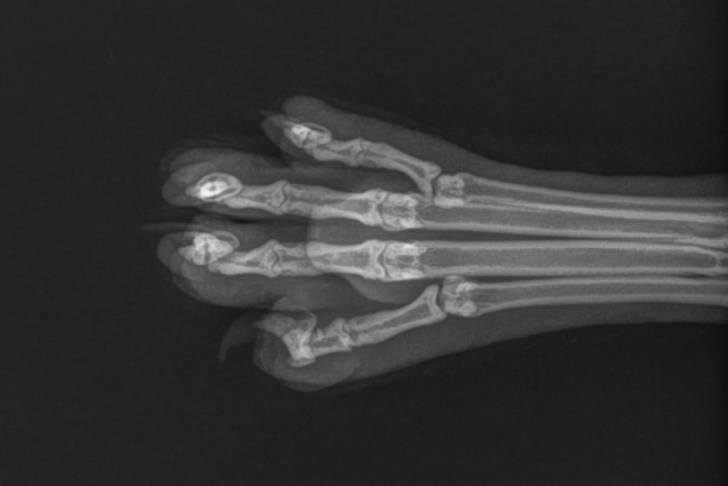

C’est le cas par exemple si son chat ne pose pas du tout un membre au sol : je l’envoie alors systématiquement vers son vétérinaire, pour que celui-ci puisse effectuer les examens qui s’imposent (par exemple une radiographie).